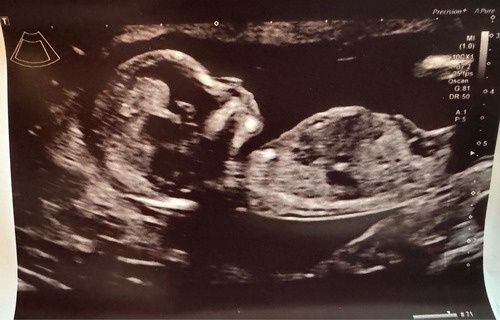

13 weken en 3 dagen